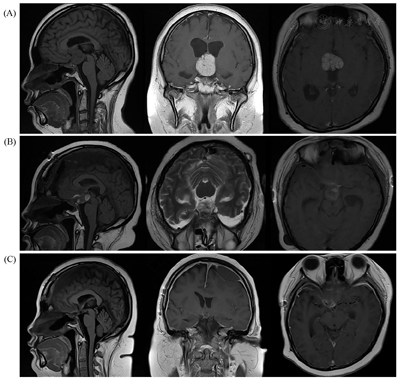

患者女性,22岁,因"头痛伴停经1年余,发现血糖升高7个月"之主诉于2018年1月入住本科。1年前因"头痛伴停经"诊断为"颅咽管瘤",10个月前在国外医院检查,晨8∶00血皮质醇14.0 μg/dl(参考范围5.0~28.0 μg/dl,下同)、促甲状腺激素(TSH)2.62 μIU/ml(0.5~4.5 μIU/ml)、FT4 0.9 ng/dl(0.8~1.8 ng/dl),行头颅磁共振(MRI)三维重建检查,诊断为"颅咽管瘤",行"经鼻蝶窦肿瘤切除术"联合"头颅穿孔减压术+去除肿瘤囊性部分"治疗,手术病理示:"乳头型颅咽管瘤(BRAF V600E突变阳性)",术后出现腺垂体功能减退、视野缺损及尿崩症等一系列相关并发症,分别给予"氢化可的松、左甲状腺素钠、去氨加压素"等药物治疗,临床症状好转(图1)。8个月前再次因"头痛"在另一国外医院诊断为"脑积水",给予"脑室腹腔分流置管术"治疗(图2)。7个月前出现精神差、偶有幻觉、短时记忆受损,复查发现"颅内肿瘤增大",于国外当地医院行放射治疗30次(放疗累积总剂量为54 Gy),为防治"脑水肿"给予口服"地塞米松4~8 mg/d"2月余,逐渐出现食欲增大、血糖增高,多次监测空腹血糖>8 mmol/L(3.9~6.1 mmol/L),伴体重增加、嗜睡、少动,未予药物治疗。4个月前再次复查"颅内肿瘤体积增大",于国外医院行"开颅肿瘤切除术"(图3),术后停用"地塞米松",改为"泼尼松40 mg/d"治疗,逐渐减量;治疗过程中逐渐出现肥胖,体重共增加约50 kg,腹部及四肢皮肤出现宽大紫纹,监测血糖升高,空腹血糖最高达15~16 mmol/L,自服"二甲双胍1.0 g/d",未规范治疗。

注:(A)术前;(B)术后;(C)术后3个月

本病例有典型的颅咽管瘤的症状和影像学表现,术前头颅CT和MRI表现为鞍区以实性为主的囊实性中心病灶,诊断为"颅咽管瘤",经历了第1次手术治疗(图1),手术方式选择了"经鼻蝶窦肿瘤切除术"加"头颅穿孔减压术",主要的目的是为了尽可能地保护下丘脑、垂体和视交叉等重要结构功能,然而术后复查发现鞍区肿瘤未完全清除(图1C)。术后3个月"颅咽管瘤复发",行放射治疗;术后半年再次复查"颅内肿瘤体积增大",进行第2次手术治疗,手术方式选择了"开颅肿瘤切除术"(图3)。临床医生需根据肿瘤的位置、大小、生长方式以及与周围结构的毗邻关系等综合评估,以选择手术方式[3,4]。